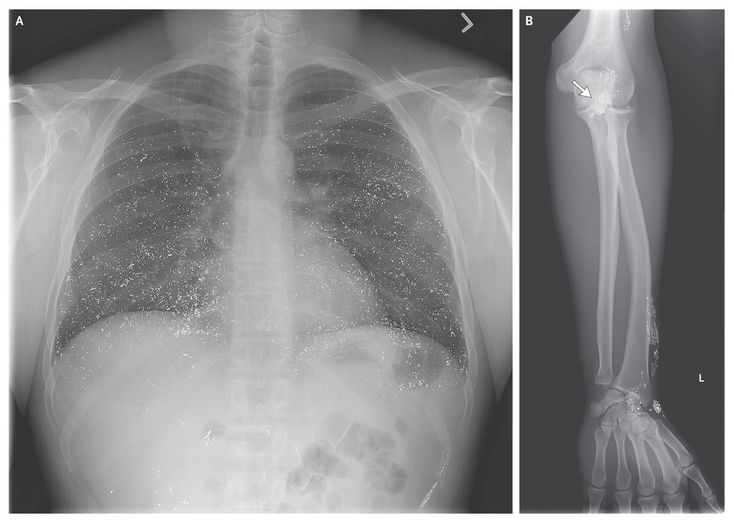

A 40-year-old man presented with headache, dry cough, and dyspnea that had begun 3 days earlier. Physical examination revealed labile mood, intention tremor, and tender subcutaneous nodules on the left forearm. The oxygen saturation was 92% while he was breathing 2 liters of oxygen per minute through a nasal cannula. A chest radiograph (Panel A) revealed innumerable small, high-density opacities diffusely distributed throughout both lungs. Laboratory testing revealed a urine mercury level of 1249 μg per liter (reference range, 0 to 10) and a serum mercury level of more than 160 μg per liter (798 nmol per liter; reference range, 0 to 10 μg per liter [0 to 50 nmol per liter]). The patient reported cutaneous exposure to mercury while exploring his recently deceased father's old gun box; liquid mercury is sometimes used to clean lead from gun barrels and chambers. A radiograph of the left forearm and wrist showed metallic opacities in the soft tissues that corresponded to the subcutaneous nodules found on examination and followed the course of superficial veins (Panel B, arrow). The clinical picture was consistent with self-injection of mercury both intravenously and subcutaneously. The patient was treated with chelation therapy with sodium 2,3-dimercapto-1-propanesulphonic acid (DMPS). By hospital day 5, the tremor had resolved, and he was less emotionally labile. On repeat testing, the urine mercury level was 692 μg per liter. Psychiatric consultation was obtained, and the patient was transferred to an inpatient psychiatric unit.